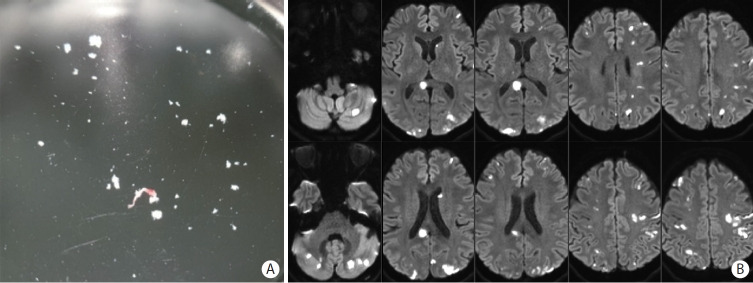

Cancer can induce hypercoagulability, which may lead to stroke. This occurs when tumor cells activate platelets as part of their growth and metastasis. Tumor cells activate platelets by generating thrombin and expressing tissue factor, resulting in tumor cell-induced platelet aggregation. Histopathological studies of thrombi obtained during endovascular thrombectomy in patients with acute stroke and active cancer have shown a high proportion of platelets and thrombin. This underscores the crucial roles of platelets and thrombin in cancer-associated thrombosis. Cancer-associated stroke typically occurs in patients with active cancer and is characterized by distinctive features. These features include multiple infarctions across multiple vascular territories, markedly elevated blood D-dimer levels, and metastasis. The presence of cardiac vegetations on echocardiography is a robust indicator of cancer-associated stroke. Suspicion of cancer-associated stroke during endovascular thrombectomy arises when white thrombi are detected, particularly in patients with active cancer. Cancer-associated stroke is almost certain when histopathological examination of thrombi shows a very high platelet and a very low erythrocyte composition. Patients with cancer-associated stroke have high risks of mortality and recurrent stroke. However, limited data are available on the optimal treatment regimen for stroke prevention in these patients. Thrombosis mechanism in cancer is well understood, and distinct therapeutic targets involving thrombin and platelets have been identified. Therefore, direct thrombin inhibitors and/or antiplatelet agents may effectively prevent stroke recurrence. Additionally, this strategy has potential benefits in cancer treatment as accumulating evidence suggests that aspirin use reduces cancer progression, metastasis, and cancer-related mortality. However, clinical trials are necessary to assess the efficacy of this strategy involving the use of direct thrombin inhibitors and/or antiplatelet therapies.